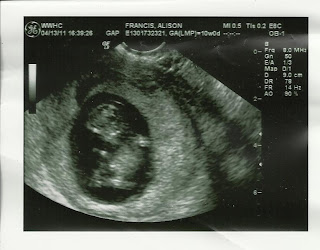

Jeff and I are thrilled to announce Baby #2 is on the way! He or she will make their arrival early November and we feel extremely blessed! I am happy to be approaching the end of the first trimester. With the end of the first trimester, I hope it will be the end of lots of sickness too (I will spare you the details).

So cool that we are able to see so many details so early (profile pic of the face also showing 2 arms and 2 legs!). I cannot wait to meet this little guy or gal!

Only 6 more months to go... Baby Francis #2 will be here before we know it!